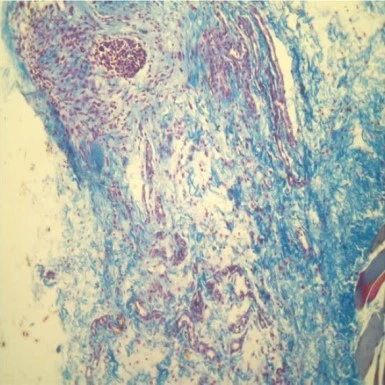

При имплантации нитей из полидиоксанона (PDO) и поли-L-молочной кислоты (PLLA) в кожу спины крыс наблюдались статистически значимое усиление синтеза коллагеновых и эластиновых волокон, а также запуск ангиогенеза (табл. 1) (рис. 6, 7)7.

Рис. 6. Неоколлагеногенез и неоэластогенез в дерме кожи над имплантированной нитью из поли-L-молочной кислоты на 90-е сутки. Коллагеновые волокна окрашены в синий, эластиновые – в красный цвет7.

...

Рис. 7. Участок дермы над имплантированной нитью из полидиоксанона на 90-й день эксперимента. Увеличение доли эластиновых волокон (красный цвет) по отношению к коллагеновым (синий цвет) в дермальном слое7.